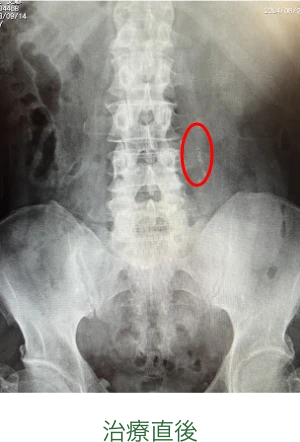

治療効果

一回の衝撃波治療により粉々に破砕され、後日結石が消失しています(赤で囲った部分)